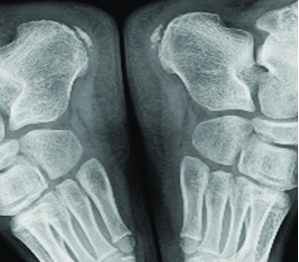

The physical examination at the final presentation to the hospital revealed a calendar age of 13 years 1 month, height 141 cm (-2.06 SDS) body weight 28.4 kg (-2.62 SDS), weight according to height 81%, and testis volumes of 5/5. There was pain in both heels increasing with palpation but with no increase in temperature, hyperaemia or swelling. He could not put his weight on his heels when walking. Laboratory tests revealed haemoglobin 13.4 gm/dL, leukocytes 5420/μL, and thrombocytes 218.000/μL with no atypical cells in the peripheral smear. The lateral foot graph revealed a sclerotic and fragmented apophysis [Table/Fig-1,2]. The patients GH treatment was continued, and he was recommended bed rest and in case of excessive pain the patient was advised nonsteroidal anti-inflammatory drugs. Follow up was undertaken jointly with the Department of Orthopaedics. After three months of follow up the pain in both heels and limping was regressed.

Fragmentation of both apophyses.